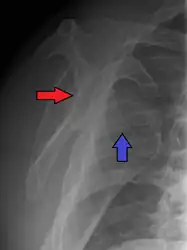

A Hill–Sachs lesion is an impaction of the head of the humerus left by the glenoid rim during dislocation.[5] Hill-Sachs deformities occur in 35–40% of anterior dislocations. They can be seen on a front-facing X-ray when the arm is in internal rotation.[8] Bankart lesions are disruptions of the glenoid labrum with or without an avulsion of bone fragment.